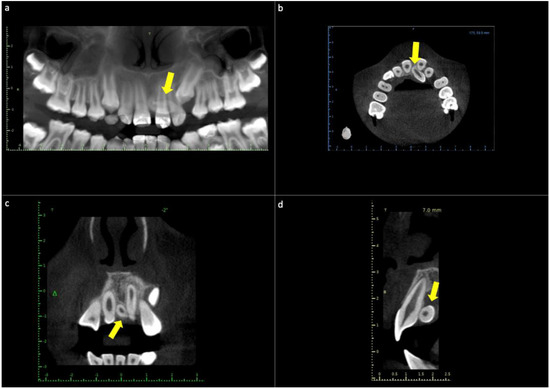

2.2. Case Report 2

| Case Report 2 | Female | Conoid mesiodens, included, vertical position, located between teeth 1.1 and 2.1 | 49 years old | Radiographic finding | Asymptomatic |